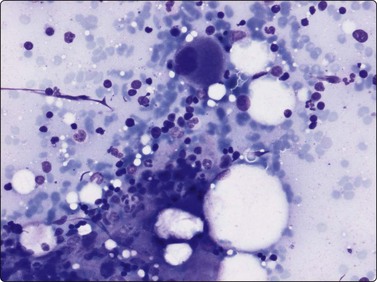

Tumors of vascular origin

Fine needle aspiration of hemangioma of any type yields plenty of venous blood. Smears may contain a few strands of endothelial cells with pale, spindly nuclei (Fig. 15.52). Macrophages, hemosiderin pigment and fibroblasts may be present if thrombosis has occurred. Most angiosarcomas are cutaneous tumors; only a minority are deep-seated. The cytologic features of angiosarcoma are variable. The cell population may be predominantly spindled, pleomorphic or epithelioid (Fig. 15.53A, B). A correct diagnosis is often not possible without immunocytochemical confirmation (CD31, CD34 and Fli-1) that the tumor cells are of endothelial origin (Fig. 15.53C). In epithelioid variants of angiosarcoma, EMA and keratin antibodies are often positive. The variable cytologic features in angiosarcoma have been described in several recent papers.65-67 Angiosarcoma of the breast is illustrated in Chapter 7 and of the spleen in Chapter 11.

image image image

Fig. 15.53 Angiosarcoma

(A) In this example, the smear population is predominantly of atypical spindle cells; differentiation from other spindle cell sarcomas requires immunostaining (H&E, LP); (B) Epithelioid pattern of gland-like cluster of malignant cells with rounded nuclei (MGG, HP); (C) A correct diagnosis is often not possible without immunocytochemical confirmation that the tumor cells are of endothelial origin (cell block, CD34, immunoperoxidase, HP).